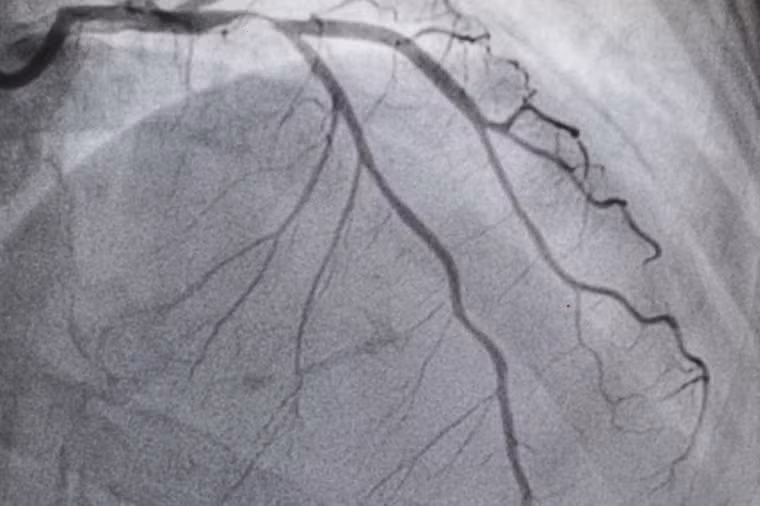

Bệnh tim mạch vành (thiếu máu cục bộ tim) là căn bệnh đáng sợ gây tử vong hàng đầu trên toàn thế giới, theo Tổ chức Y tế Thế giới (WHO). Bệnh tim mạch và đột quỵ chiếm tổng cộng 15,2 triệu ca tử vong trong năm 2016.